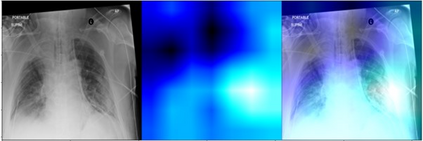

Deep learning (DL) analysis of Chest X-ray (CXR) and Computed tomography (CT) images has garnered a lot of attention in recent times due to the COVID-19 pandemic. Convolutional Neural Networks (CNNs) are well suited for the image analysis tasks when trained on humongous amounts of data. Applications developed for medical image analysis require high sensitivity and precision compared to any other fields. Most of the tools proposed for detection of COVID-19 claims to have high sensitivity and recalls but have failed to generalize and perform when tested on unseen datasets. This encouraged us to develop a CNN model, analyze and understand the performance of it by visualizing the predictions of the model using class activation maps generated using (Gradient-weighted Class Activation Mapping) Grad-CAM technique. This study provides a detailed discussion of the success and failure of the proposed model at an image level. Performance of the model is compared with state-of-the-art DL models and shown to be comparable. The data and code used are available at https://github.com/aleesuss/c19.